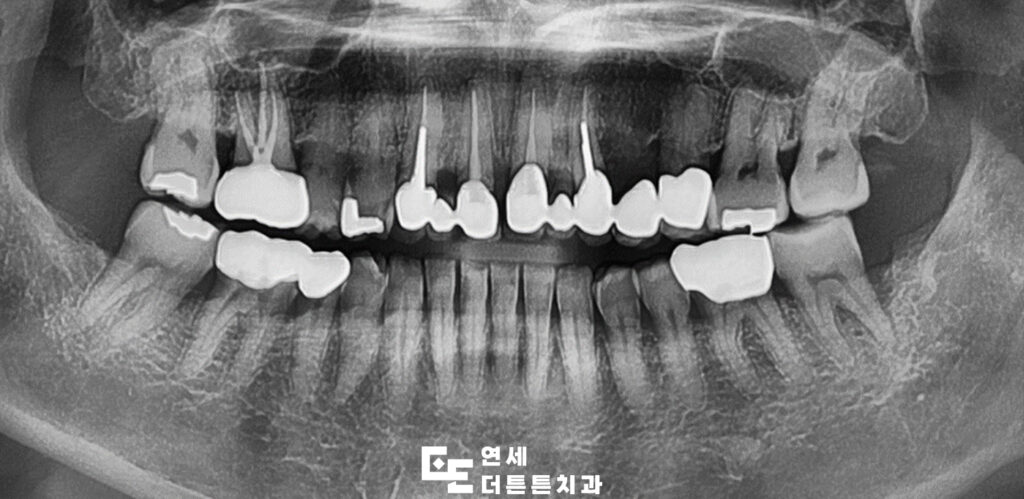

이미 치아가 상실된 부위에는 임플란트 식립을 먼저 시행하였으며 전반적인 조화를 고려해 지르코니아 브릿지로 최종 보철을 완성하였습니다.

치아 손상 범위가 넓거나 형태 개선이 필요한 경우에는 치아 전체를 덮는 크라운 치료가 적합한데 최근 심미성과 강도를 동시에 만족시키는 재료로 지르코니아가 많은 주목을 받고 있습니다.

지르코니아는 자연치와 유사한 색감과 투명도를 구현할 수 있으며 내구성이 뛰어나 장기간 사용에도 안정적인 장점이 있습니다. 기능적인 부분과 심미적인 부분을 함께 고려해야 하는 앞니 보철에 적합한 재료라고 볼 수 있습니다. 또한 금속이 포함되지 않아 시간이 지나도 잇몸 변색 가능성이 낮고 알레르기 반응 위험이 적어 체질적으로 민감한 분들께도 부담이 적은 편입니다.

기능 회복과 함께 심리적인 만족도 역시 크게 향상되어 웃는 모습에 자신감을 되찾을 수 있고, 자연스러운 인상 변화는 대인관계나 사회생활에도 긍정적인 영향을 줄 수 있습니다. 다만 모든 환자에게 동일하게 적용될 수는 없으며 보철물을 지지할 치아와 잇몸의 건강 상태가 우선적으로 확보되어야 합니다. 뿌리나 잇몸에 문제가 있는 경우에는 사전 치료가 반드시 필요할 수 있습니다. 이번 환자분 또한 작은 어금니에 지르코니아 크라운을 계획하였으나 뿌리 쪽 염증이 심한 상태였기 때문에 신경치료를 먼저 진행한 후 보철 치료를 마무리할 수 있었습니다.